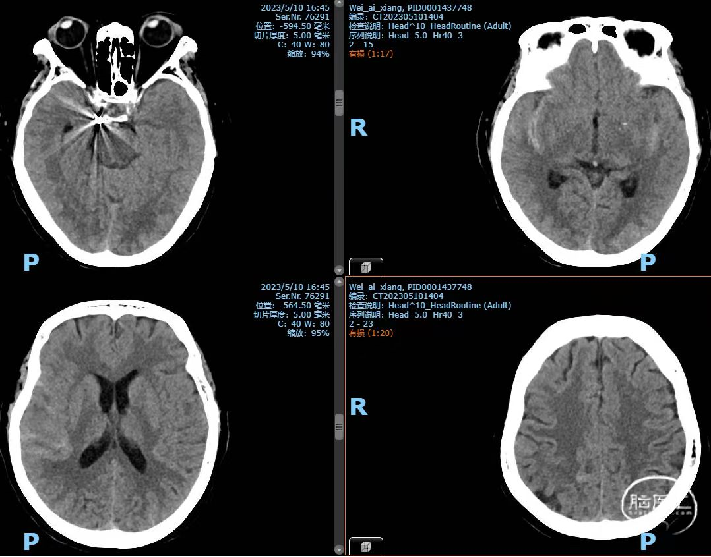

病例4

一般项目:姓名:闫月君 性别:女 年龄:64,因“右侧颈内动脉动脉瘤栓塞后半年”于2023-5-15 11:59 非急诊入院。

患者自诉半年前在广西壮族自治区人民医院桃源区行右侧颈内动脉C6动脉瘤血流导向密网支架(Pipeline)植入术,术后病情好转出院,现为复查造影入院。

诊断:1、左侧颈内动脉C6段动脉瘤 2、右侧颈内动脉C6段动脉瘤血流导向密网支架植入术后

首次RICA An ped支架植入,瘤内造影剂明显滞留。

诊疗计划

造影检查,备nuva 密网支架植入治疗残留动脉瘤或左侧C6段动脉瘤

2023-5-19手术

右侧ICA造影:动脉瘤正处于继续愈合状态,无需再处理

左侧C6多发动脉瘤

支撑系统:6F Envoy DA导引导管

微导管/导丝:Synchro微导丝携带支架导管定位于左侧大脑中动脉,

支架:泰杰Nuva密网支架TJED-4.5-16,

术后第一天

男,60岁,因“反复头痛10余年”于2016-05-16 16:14 非急诊步行入院。

NS(-)

2023-5-8 MRI+MRA+DWI:右侧颈内动脉C6段中-重度狭窄,右侧大脑后动脉P3段局部管腔轻度狭窄。考虑左侧颈内动脉C4、C6段动脉瘤。

初步诊断:1.左侧颈内动脉C4、C6段动脉瘤

2.右侧颈内动脉C6段中-重度狭窄

3.右侧大脑后动脉P3段局部轻度狭窄

造影检查,备颅内动脉瘤栓塞术+nuva 密网支架植入

通路:中天医疗6F远端通路导管、Neuron MAX 6F 088导引导管

微导管微导丝:泰杰TJMC18微导管,FATHOM-14微导丝 200CM

及 300CM

其他:Nuva TJED-4.5-25、心凯诺颅内球囊扩张导管 4.0*15mm